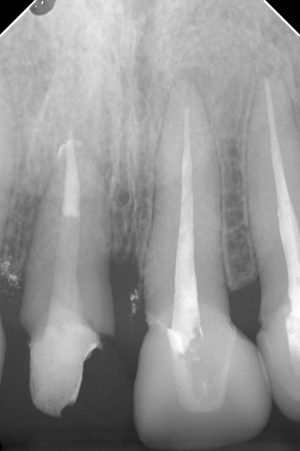

歯が水平にぽっきり折れてしまった症例です。

頬側の歯質が歯槽骨のはるかしたで折れてしまっていたため、抜歯と言われたとの事で来てくださいました。

根管治療時。コーンフィットしています。

築造時。

骨はもう出来ていますね。

術後2年。

問題なく経過しています。